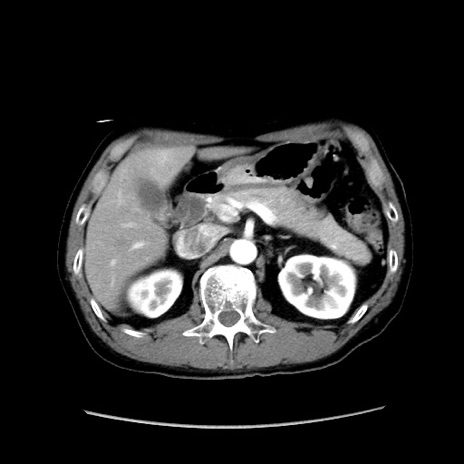

症例37(横断像)

【症例】40歳代 男性

【主訴】腹痛

【現病歴】4時間ほど前に電車に乗車中に臍部上より腹痛出現。徐々に増悪し起立困難となり、救急外来受診。生ものは数日食べていない。今朝お雑煮を食べた。

【身体所見】BT 36.8℃、BP 117/84mmHg、HR 91/min、SpO2 97%、苦悶様、腹部:臍上部広範囲圧痛あり、反跳痛±

【データ】WBC 8100、CRP 0.03